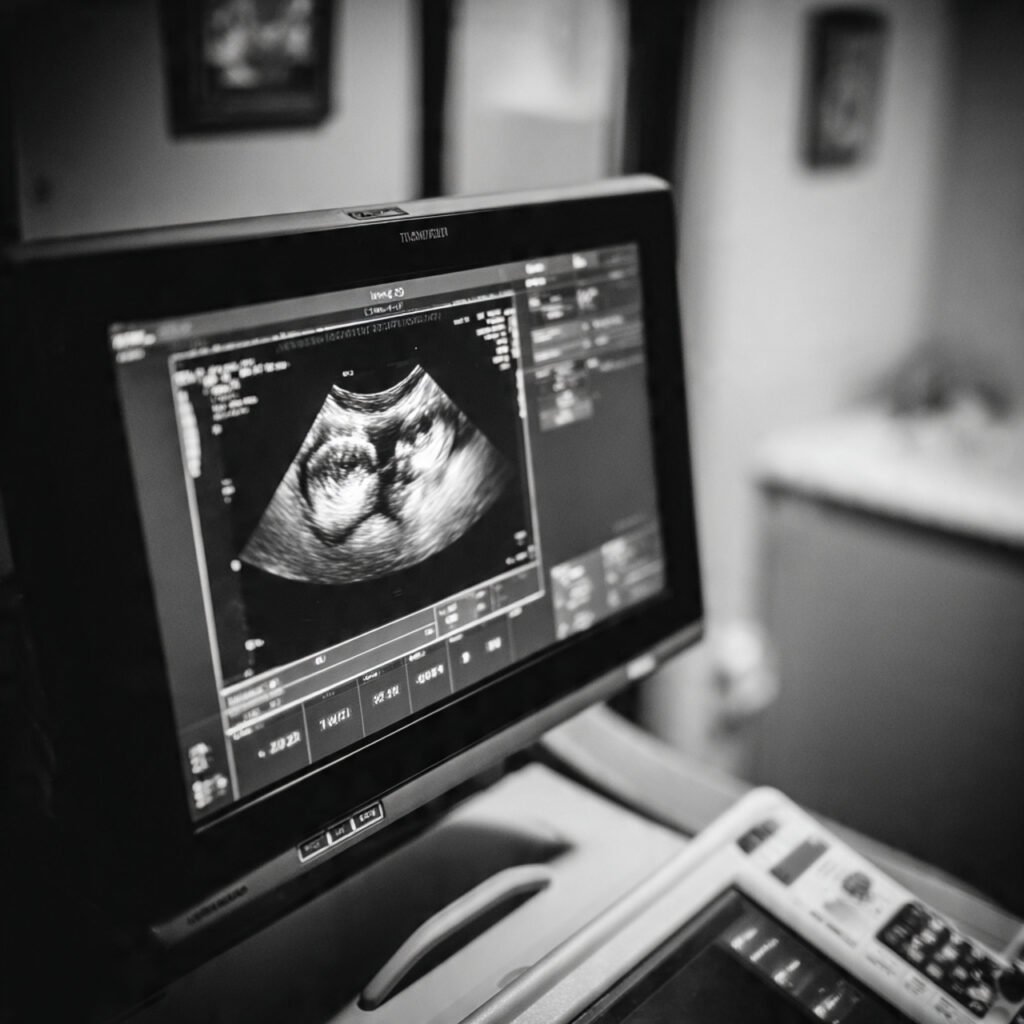

Founder of Nisarga Diagnostics, is a renowned fetal ultrasound specialist with over 20 years of expertise. An alumnus of Government Medical Colleges in Mysore and Bangalore, he also holds a D.N.B. from the National Board of Examinations, Delhi, and certification from the Fetal Medicine Foundation, London. A former Professor and HOD, he has trained countless PG students and junior radiologists, shaping the future of fetal imaging in India.